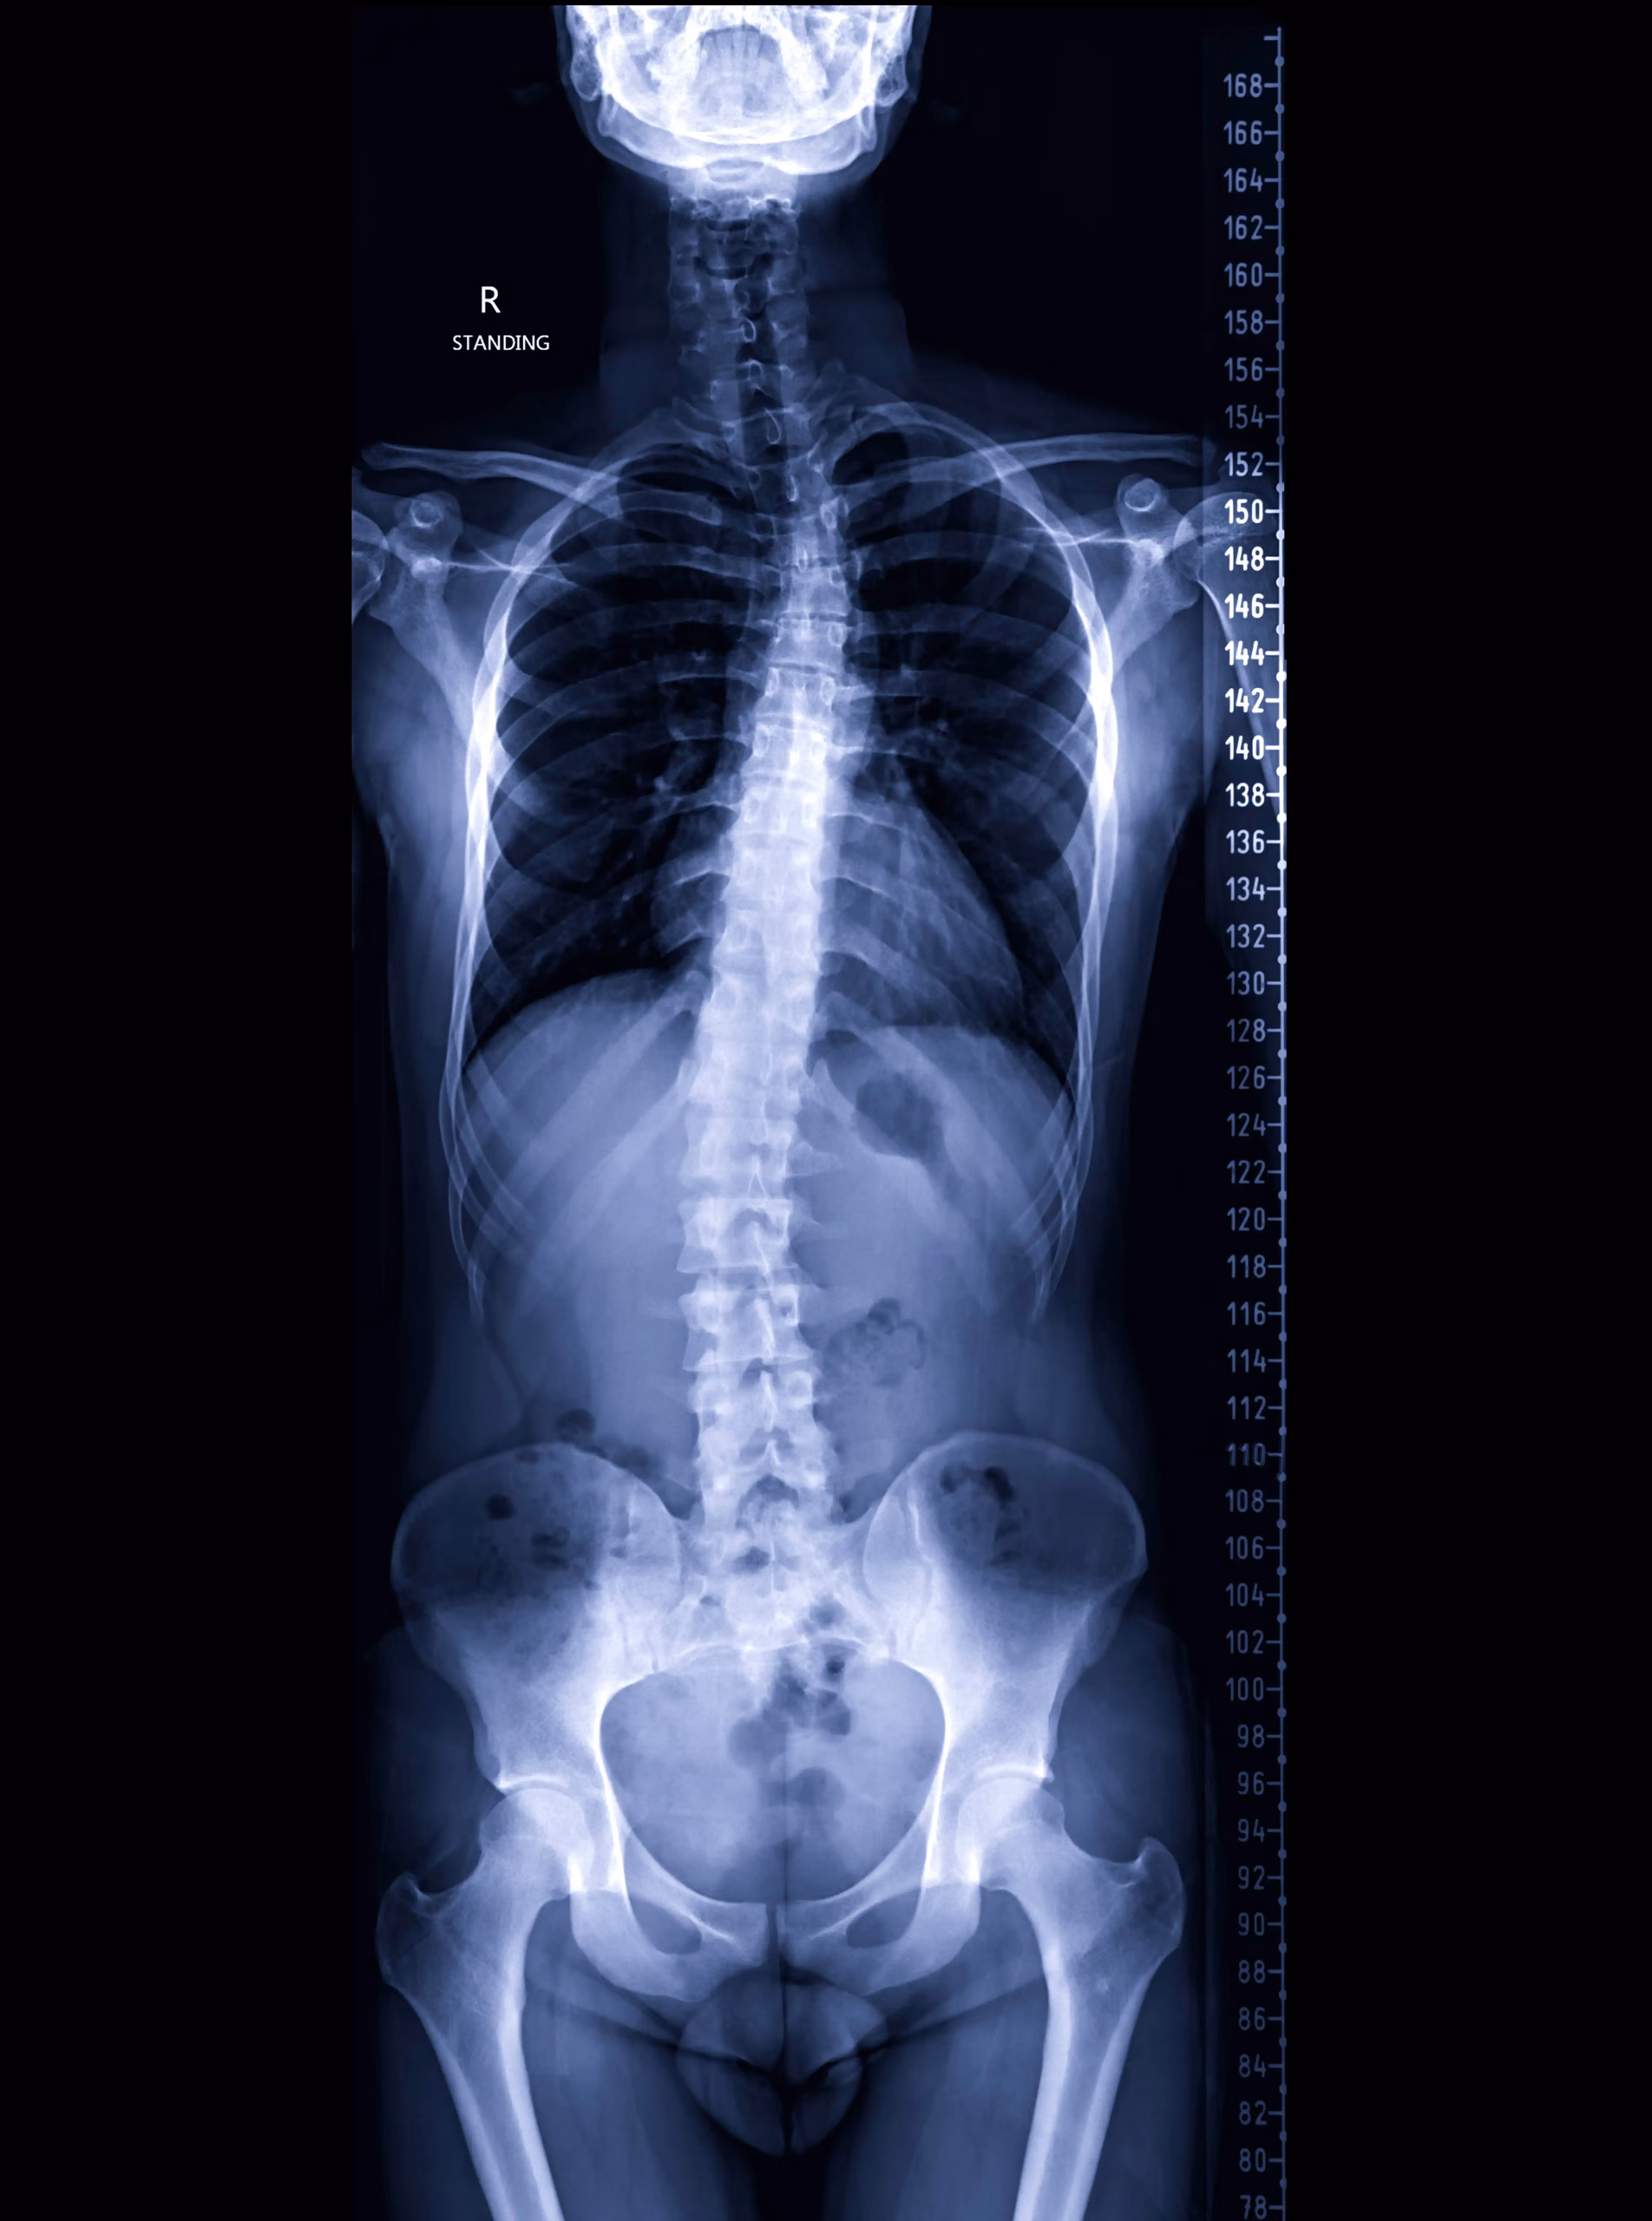

🮽 Coloană totală (stitching)

• Imagine panoramică față — evaluare scolioză

• Unghiuri scoliotice, echilibru sagital

• Evaluare pre- și post-tratament

Radiografia de coloană totală (stitching) — ce este și când se recomandă?

Radiografia totală de coloană (stitching) produce o imagine panoramică a întregii coloane vertebrale față, prin combinarea digitală a mai multor imagini. Este investigația standard pentru evaluarea scoliozei — permite măsurarea unghiurilor scoliotice (unghi Cobb), evaluarea echilibrului sagital și monitorizarea evoluției. Se recomandă la diagnostic, la controlul periodic și pre/post intervenție terapeutică.